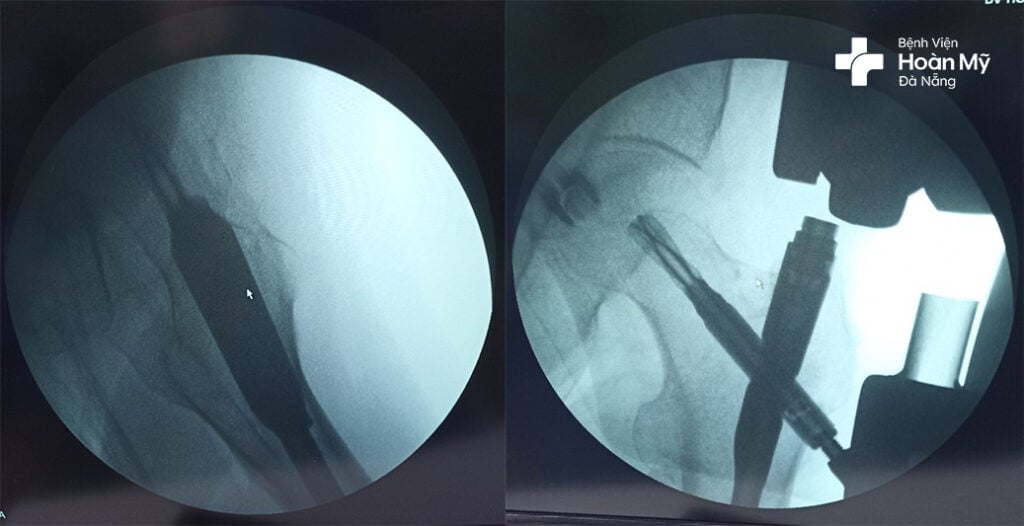

Sau khi trao đổi với người bệnh và gia đình, các bác sĩ quyết định lựa chọn phương pháp phẫu thuật đóng đinh nội tủy Gamma dưới màn tăng sáng (C-Arm) để chữa lành xương cho người bệnh.

“Với phương pháp này, bác sĩ tiến hành phẫu thuật kết hợp xương bằng cách luồn đinh vào trong ống tủy thông qua vết rạch nhỏ từ 2-4 cm trên da mà không cần phải mở ổ gãy, từ đó hạn chế nguy cơ chảy máu, nhiễm trùng, rút ngắn thời gian lành thương mà vị trí xương gãy vẫn được nắn chỉnh thẳng, vững chắc, sớm phục hồi vận động. Một điều tuyệt vời nữa là người bệnh có thể tập đi lại sớm ngay thời điểm 1 ngày sau mổ” – Ths. Bs. Phạm Duy Hải, Khoa Ngoại Chấn thương chỉnh hình – Thần kinh, Bệnh viện Hoàn Mỹ Đà Nẵng cho biết.

Hình ảnh kết hợp xương bằng đóng đinh nội tủy sau phẫu thuật cho người bệnh

Ca phẫu thuật được thực hiện thành công sau 40 phút tiến hành với vết mổ nhỏ 2-3 cm, người bệnh ít mất máu.